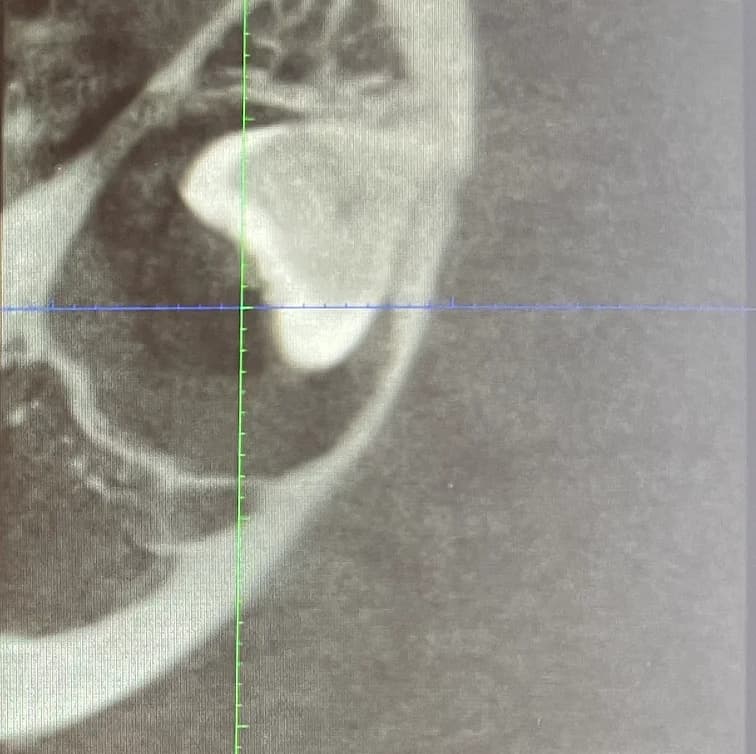

The extraction of wisdom teeth, also known as third molars, is a common dental procedure performed to remove teeth that cannot grow properly or cause dental problems. They are typically four in number and usually appear in the mouth between the ages of 15 and 25. They can fully erupt, be partially erupted, or be impacted. They typically do not have enough space in the mouth, so they are often misaligned and exert pressure on adjacent teeth, potentially causing damage. Extraction of wisdom teeth is often recommended when the teeth are impacted (trapped in the gum or bone) or causing problems such as pain, infection, tooth decay, shifting of other teeth, or the development of cysts. It is advisable to have them extracted at a young age, typically at the end of adolescence or early adulthood. Indeed, the risks increase with age, and recovery is easier at a younger age.